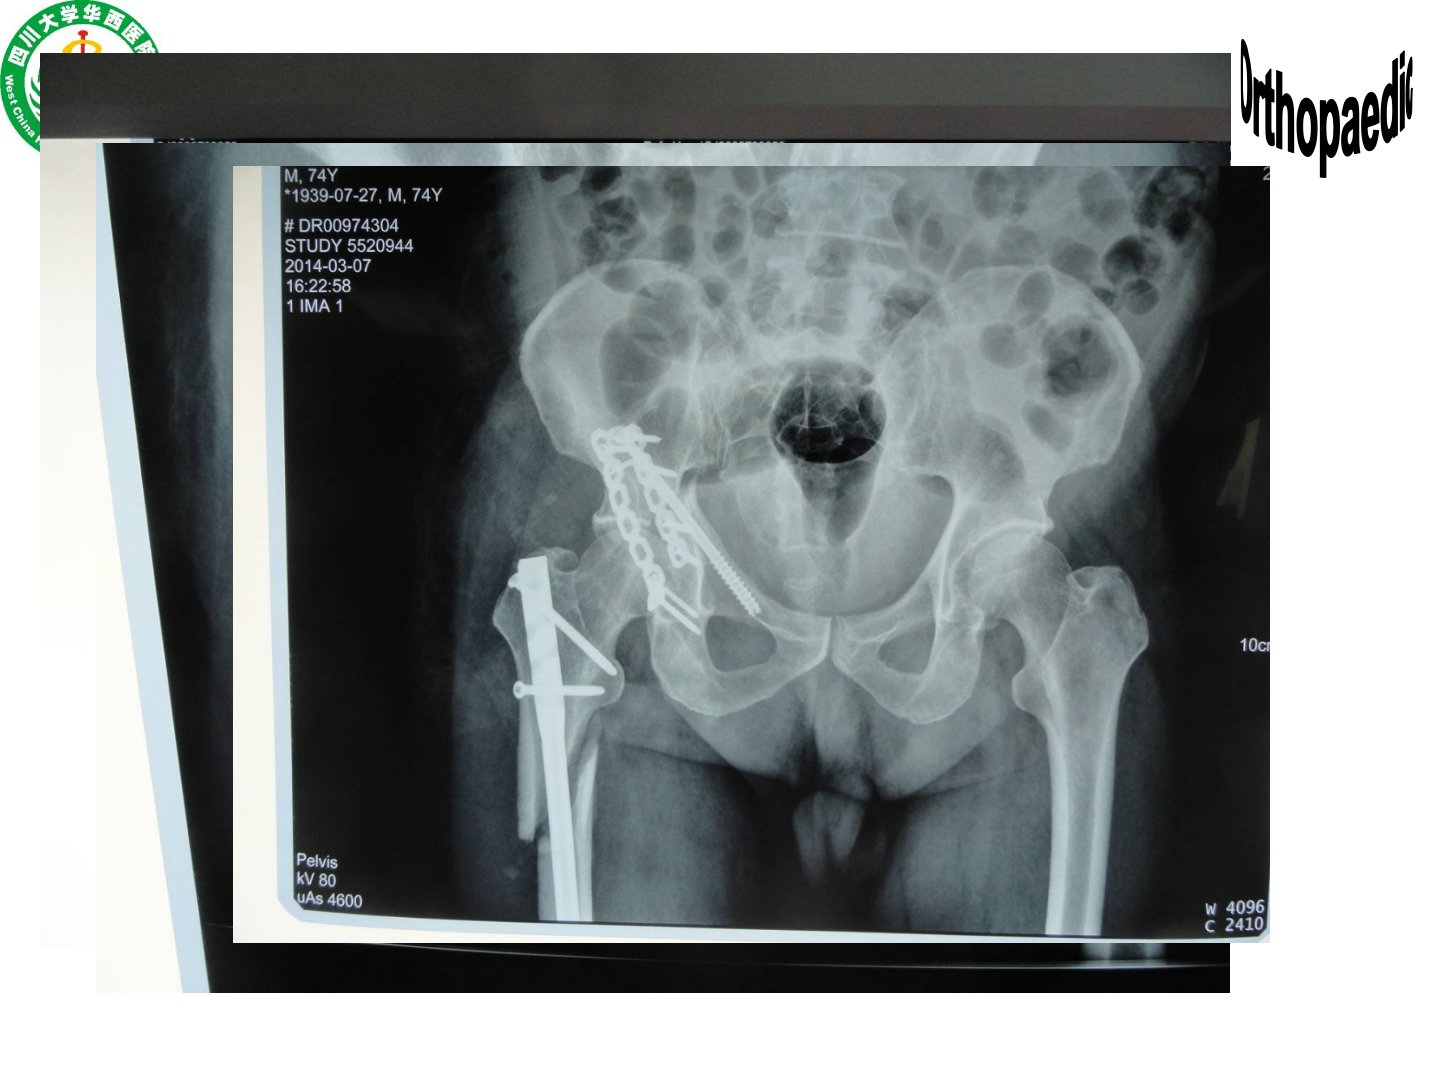

四肢骨折摘要本文由四川大学华西医院骨科黄富国介绍四肢骨折相关内容。骨折诊断需明确创伤部位、机制、时间、开放闭合情况、程度类型及并发症等。暴力机制影响骨折诊治与预后不同暴力类型(高处坠落伤、车祸伤等)有不同意义影像检查(X线、CT、MRI)对明确骨折情况、指导治疗和判断预后意义重大。骨折移位由暴力大小方向、肢体重力、肌肉牵拉导致会产生血管神经损伤等后果必须矫正的移位因骨折部位而异。骨折并发症包括骨折不愈、骨坏死、骨筋膜室综合征等。治疗原则为先保生命再保肢体最后保功能方式有非手术(复位手法、牵引、固定方式)和手术(固定方式多样)。文章还提出学习目的和要求包括掌握多种骨折的诊断治疗原则熟悉部分骨折并发症及处理了解另一些骨折的相关情况。此外详细介绍了肱骨、尺桡骨、桡骨远端、股骨、胫腓骨等部位骨折的解剖、病因、分类、临床表现、诊断及治疗原则并以患者男45岁车祸伤为例提出诊断、辅助检查、合并伤相关问题。